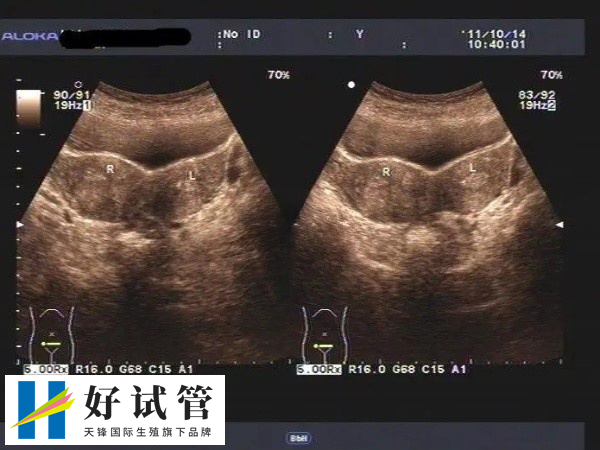

卵泡监测

促排卵期间应定期监测卵泡,指导药物调整,注射或不注射HCG监测卵泡发育情况,直至卵泡接近成熟大小(18-20cm)。同时,我们还可以通过基础体温、宫颈粘液评分、血尿激素等来监测卵泡的发育情况。大概在400-1000元之间。